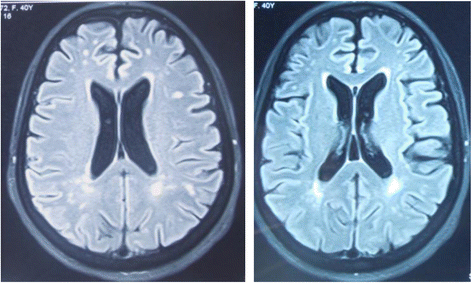

Brain MRI FLAIR sequences showing bilateral hyperintensities, affecting periventricular regions predominantly in the subcortical white matter

Fig. 1